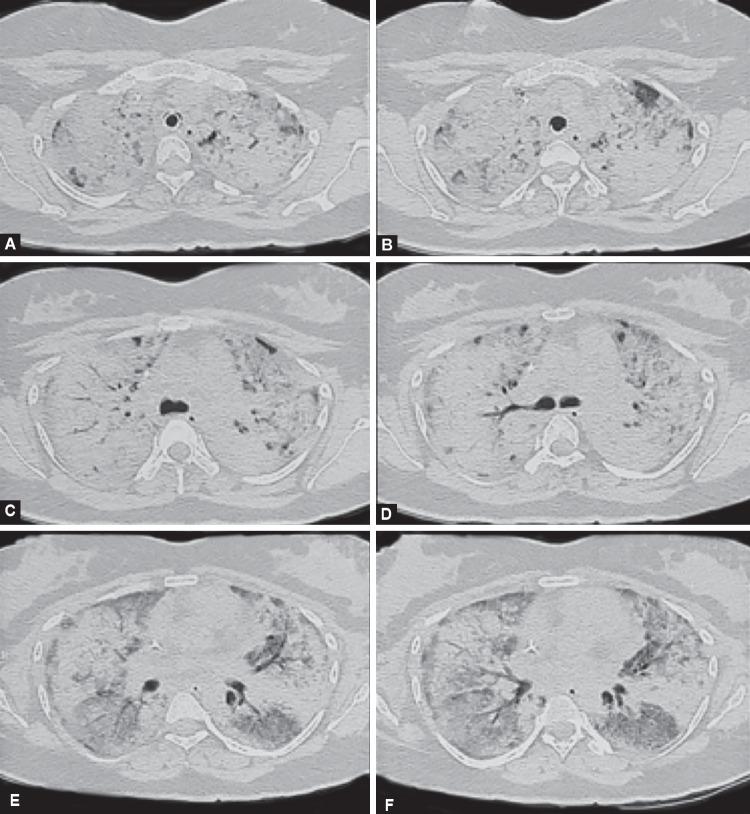

Diffuse alveolar hemorrhage (DAH) is a rare but life-threatening disease. Mortality is very high in those patients who require mechanical ventilation. Traditionally, active bleeding has been considered a contraindication for extracorporeal membrane oxygenation (ECMO) support. There is limited evidence for ECMO in DAH as rescue therapy. Herein, we describe a case of antineutrophil cytoplasmic antibodies-associated DAH with intractable hypoxemic respiratory failure. An appropriate ventilator strategy failed to improve her hypoxemia leading to imminent risk to her life. The patient was rescued with veno-venous ECMO targeting lower than usual range of anticoagulation. ECMO proved to be lifesaving in our patient who was initiated on prompt immunosuppressive therapy and plasmapheresis along with continuous veno-venous hemodiafiltration and hemodynamic support. We feel that ECMO could be considered as adjunctive therapy in severe hypoxemic respiratory failure associated with DAH after careful consideration of the risk of bleeding and a restrictive anticoagulation strategy. Goel MK, Chauhan M, Kumar A, Wadwa P, Maitra G, Talegaonkkar M, A Case of Refractory Hypoxemic Respiratory Failure due to Antineutrophil Cytoplasmic Antibodies-associated Diffuse Alveolar Hemorrhage Rescued by Extracorporeal Membrane Oxygenation. Indian J Crit Care Med 2020;24(9):879-881.

弥漫性肺泡出血(DAH)是一种罕见但危及生命的疾病。对于需要机械通气的患者,死亡率非常高。传统上,活动性出血被认为是体外膜肺氧合(ECMO)支持的禁忌证。关于ECMO用于DAH作为挽救治疗的证据有限。在此,我们描述一例抗中性粒细胞胞浆抗体相关性DAH伴难治性低氧性呼吸衰竭的病例。适当的通气策略未能改善其低氧血症,导致其生命面临紧迫风险。该患者采用低于常规抗凝范围的静脉-静脉ECMO进行抢救。在对患者迅速启动免疫抑制治疗、血浆置换以及持续静脉-静脉血液透析滤过和血流动力学支持后,ECMO被证明挽救了患者生命。我们认为,在仔细考虑出血风险和采取限制性抗凝策略后,ECMO可被视为与DAH相关的严重低氧性呼吸衰竭的辅助治疗。Goel MK、Chauhan M、Kumar A、Wadwa P、Maitra G、Talegaonkkar M,《一例抗中性粒细胞胞浆抗体相关性弥漫性肺泡出血所致难治性低氧性呼吸衰竭经体外膜肺氧合救治》。《印度危重症医学杂志》2020年;24(9):879 - 881。